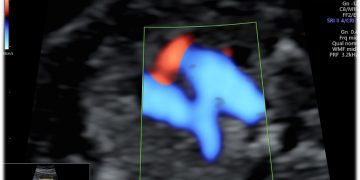

Casi del Mese di Dicembre 2024

Cari soci, finalmente on line le soluzioni dei casi del mese di Dicembre. Grazie a Sara Zullino e Mara Albanese!! Caso 1 - video [pdf-embedder url="https://www.sieog.it/wp-content/uploads/2024/12/Casodelmese_Dicembre2024caso-risposte_gineco.pdf"...